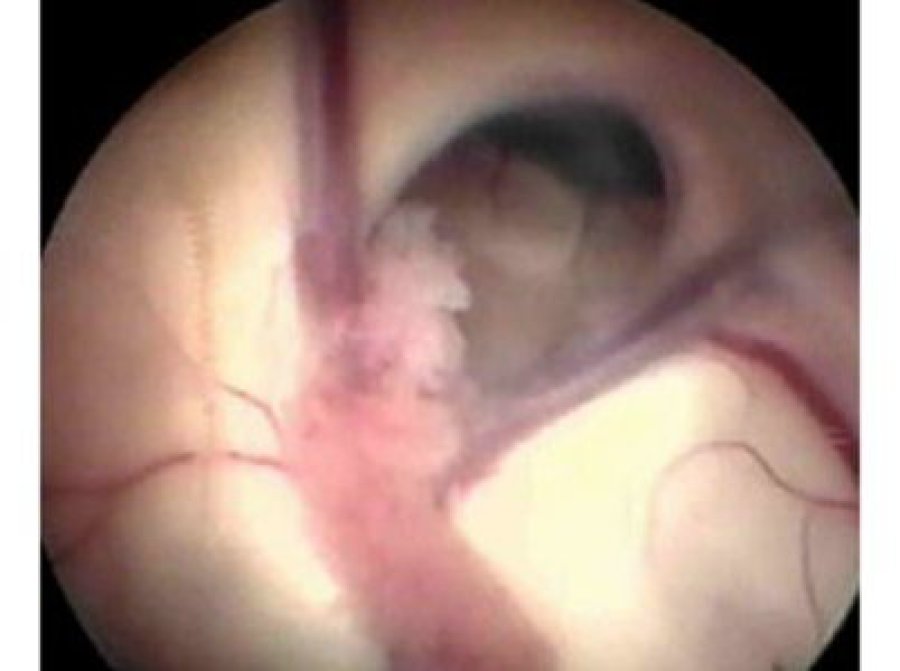

Learn MoreTumours and Cysts

High grade, low grade, benign and non-neoplastic mass lesions of the brain and spine in adults and children